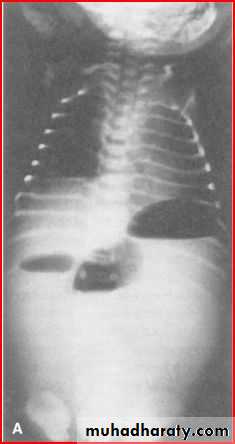

scoliosis